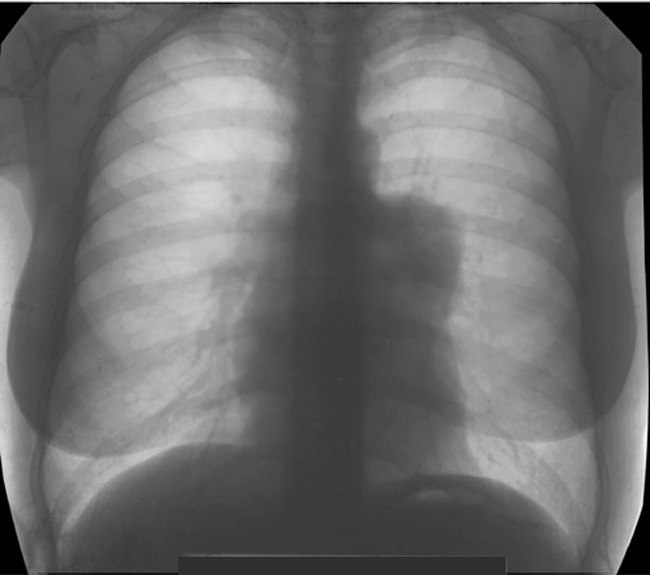

Тимомегалия: что это такое и как проявляется

Раздел: Фотоальбом решений